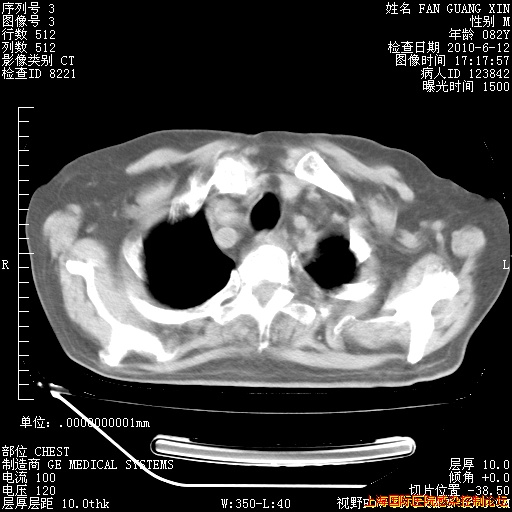

6月12日肺窗

6月12日纵膈窗